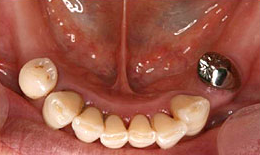

インプラント症例(9)女性 58歳

治療方法

- インプラントを6本埋め込んで、セラミックスクラウンを被せた